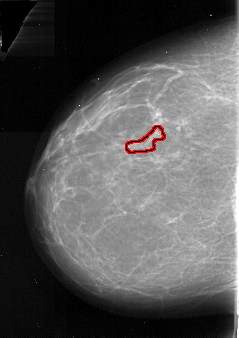

A_1083_1.LEFT_CC

LEFT_CC LINES 5056 PIXELS_PER_LINE 3571 BITS_PER_PIXEL 16 RESOLUTION 42 OVERLAY

FILE: A_1083_1.LEFT_CC.OVERLAY

TOTAL_ABNORMALITIES 1

ABNORMALITY 1

LESION_TYPE CALCIFICATION TYPE PLEOMORPHIC DISTRIBUTION LINEAR

ASSESSMENT 4

SUBTLETY 2

PATHOLOGY MALIGNANT

TOTAL_OUTLINES 1

BOUNDARY